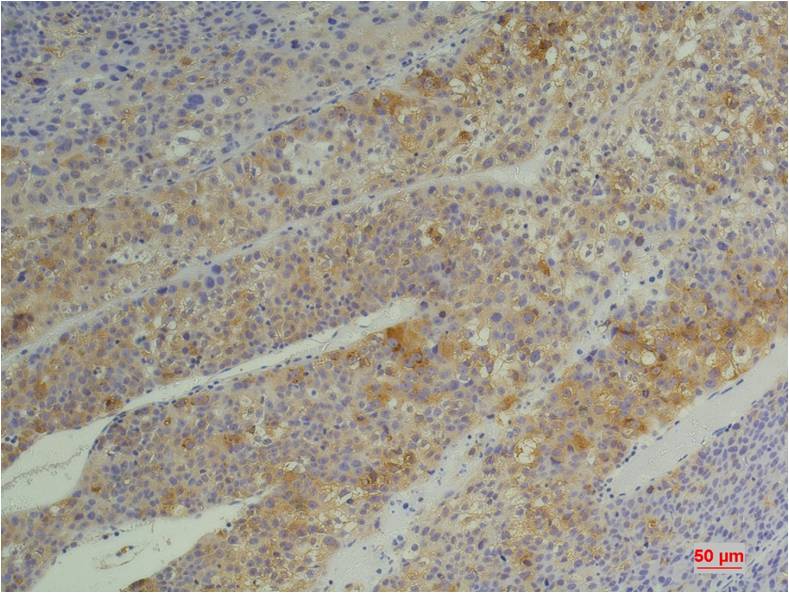

IHC 1/50-1/100 Human,Mouse,Rat